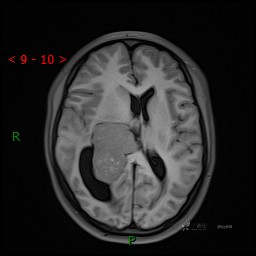

简要病史:患者于1月前无明显诱因出现视物模糊,无明显头痛头晕,无恶心呕吐,无昏迷,无肢体偏瘫等症状,就诊于当地医院头部CT考虑:右侧丘脑、脑室占位。予以对症处置后家属为求进一步诊治来我科,以“颅内占位”收入院。 起病以来,精神、饮食、睡眠欠佳,大小便正常,体力下降,体重无明显变化。

辅助检查:CT MRI

临床诊断:脑室占位

MRI平扫

CE